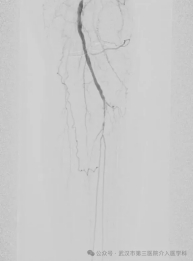

术中腘窝动脉穿刺,导丝在髂动脉会师

可以理解为一场针对血管的“微创疏通作业”。我们通过患者大腿根部一个仅有针眼大小的穿刺口,送入一根纤细的导管,直达被堵塞的下肢动脉。然后,像给轮胎打气一样,用特制的球囊扩张被堵塞的血管,撑开狭窄处,恢复血流通畅。